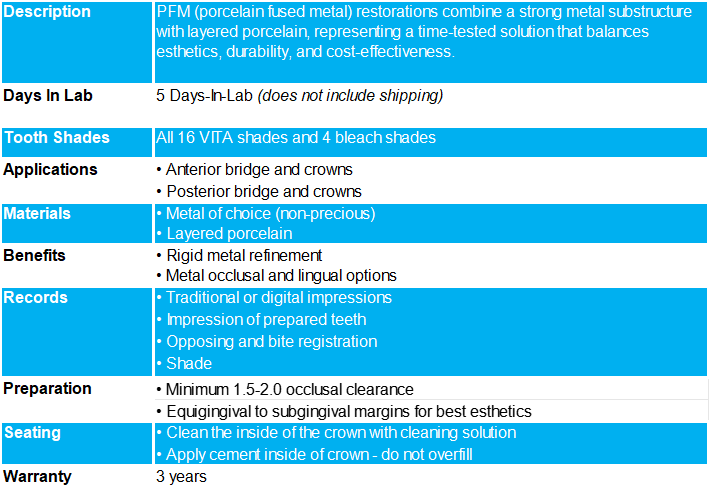

Products Description

Clinical Benefits of a pfm Crown